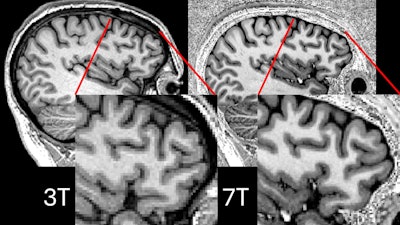

Comparison showing 3-tesla and 7-tesla scans for the same participant. Image courtesy of P Simon Jones, PhD, of the University of Cambridge.

Ultrahigh field 7-tesla MRI brain scans offer more detailed resolution and can help detect lesions in patients with drug-resistant epilepsy better than 3-tesla MRI devices, according to the group. But even though 7-tesla MRI has benefits over 3-tesla, it can still be limited by the signal dropouts. Klodowski and colleagues and a team from the Université Paris-Saclay in France tested the parallel transmit technique, which uses eight transmitters around the brain rather than just one to avoid these dropouts.